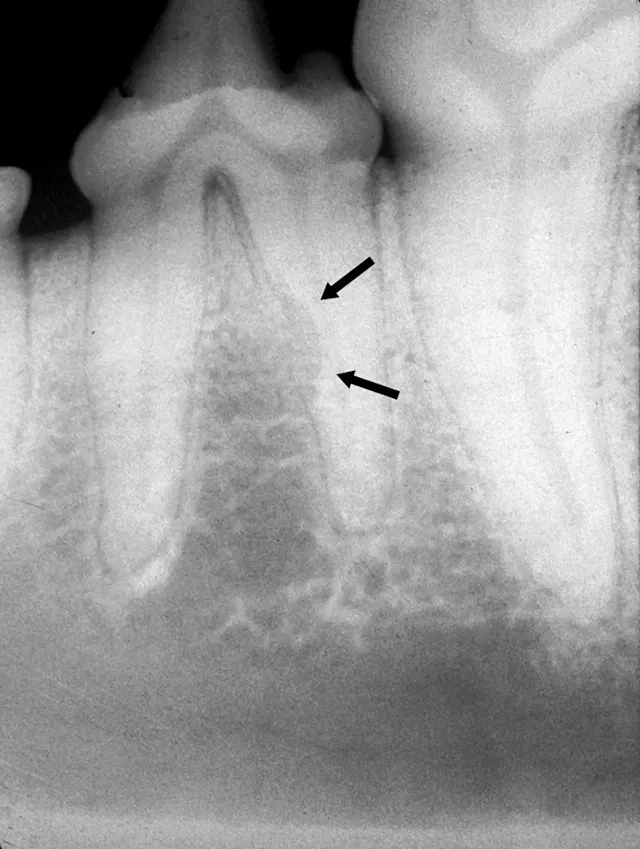

Intraoral radiograph of the left mandibular fourth premolar; the distal root is affected by external resorption that has not extended into the oral cavity.

When resorption begins deep in the alveolus on the root surface, the periodontal ligament and root parts may be replaced with bone- or cementum-like tissue via a noninflammatory process. If the lesion does not appear to extend into the oral cavity, it can be monitored for progression q6mo. Watchful waiting is indicated in cases with minimal root involvement not extending into the oral cavity; follow-up intraoral radiography q6–12mo is recommended accordingly. If the resorption area approaches or extends into the oral cavity, extraction is the treatment of choice.